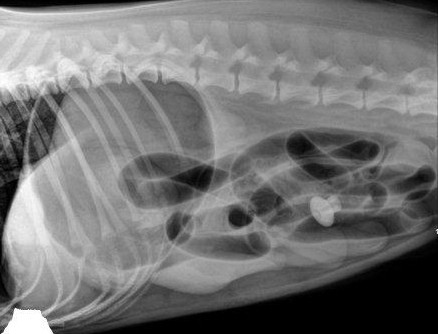

Часто проводят медицинский осмотр и анализы крови, чтобы исключить другие причины наблюдаемых клинических признаков. Пальпация живота важна для диагностики непроходимости, но для подтверждения часто требуется расширенная диагностика. Рентгенограмма брюшной полости (рентген) является наиболее распространенным диагностическим тестом, который помогает визуализировать признаки ИТ/обструкции. Часто сам ИТ не виден, но видны последствия обструкции инородным телом. К ним относятся жидкость и газ, скапливающиеся позади или внутри инородного тела. Если рентгенограммы не являются диагностическими, часто может быть выполнено УЗИ брюшной полости, чтобы помочь в определении причины клинических признаков.

Рентгенограмма брюшной полости (рентген) собаки, которая съела несколько гвоздей, которые вы можете видеть в ее желудке.